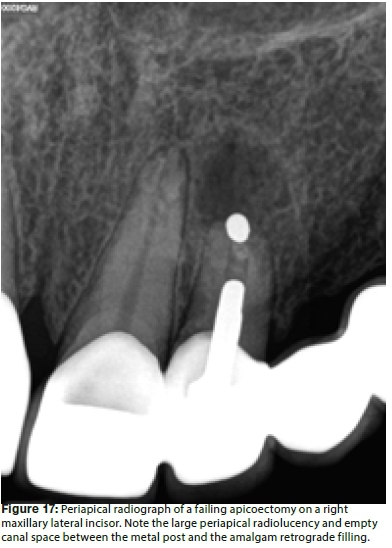

Figure 17 illustrates a periapical radiograph of a failing apicoectomy on a right maxillary lateral incisor of a 45 year old female patient, three years after surgery. The tooth is part of a six-unit fixed bridge. It was evident that an amalgam retrograde was placed, but the surgeon failed to remove all the bacteria from the entire root canal system before placing the retrograde filling material. Several authors have confirmed that if the root canal space is not completely instrumented or inadequately treated, the outcome will be poor.34,35 After anaesthesia, a submarginal flap was designed and the flap reflected using a micro-scalpel and micro-surgical elevators, under 10X magnification. Figure 18 depicts the clinical view after atraumatic reflection of the flap and clearly shows evidence of a large periapical granuloma or cystic lesion associated with the apex of the tooth. mented or inadequately treated, the outcome will be poor.34,35